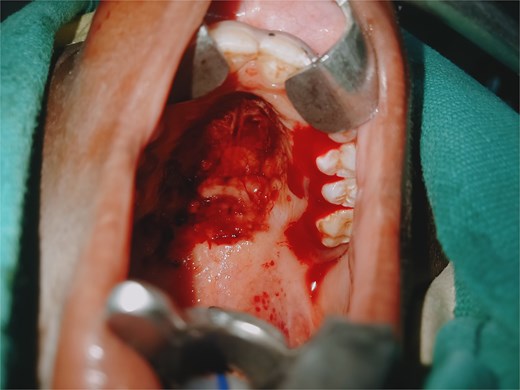

She was taken for examination under anesthesia where nasopharyngoscopy demonstrated extensive mucosal lacerations involving the inferior turbinate, nasal floor, nasopharyngeal roof and posterior wall, with active bleeding (Fig. 3). Additional traumatic injuries were observed on the soft palate and the left posterior tonsillar pillar (Fig. 4). Blood clots were evacuated, through irrigation, and hemostasis was achieved through gauze compression, suturing, and electrocautery, followed by anterior and posterior nasal packing. She received two units of blood and was stabilized before transfer to the pediatric oncology ward.

Oral cavity examination showing actively bleeding lacerations on the soft palate and left tonsillar pillar.